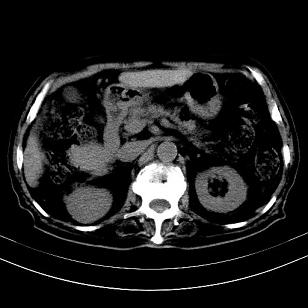

考虑肝右叶变异肝癌并肝内转移

肝癌肝转移

考虑外生性肝癌伴肝转移

支持肝右叶外生型肝癌并肝内转移